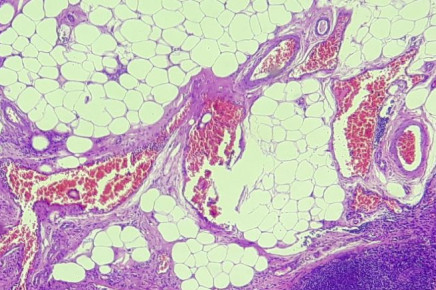

Biópsia de Congelação (Pré-Operatória)

Procedimento realizado no momento em que está ocorrendo a cirurgia, e permite ao patologista definir na maior parte das vezes se a doença é benigna ou maligna, possibilitando ao cirurgião optar pela melhor conduta cirúrgica frente ao diagnóstico microscópico.

Imagem de Biópsia de Congelação (Pré-Operatória)